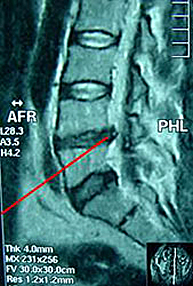

La explicación del paciente y la exploración del médico suelen ser suficientes para realizar una aproximación. Las radiografías simples no son útiles para visualizar una hernia discal pero se necesitan para descartar otras lesiones asociadas. El TAC (escáner) o la resonancia magnética son las pruebas reinas para concretar el diagnóstico y definir el tipo, tamaño y situación de la hernia. La electromiografía (EMG) es otra prueba diagnóstica que, mediante el uso de electrodos, aporta información objetiva respecto al grado de lesión que la hernia discal ha producido a la raíz nerviosa.